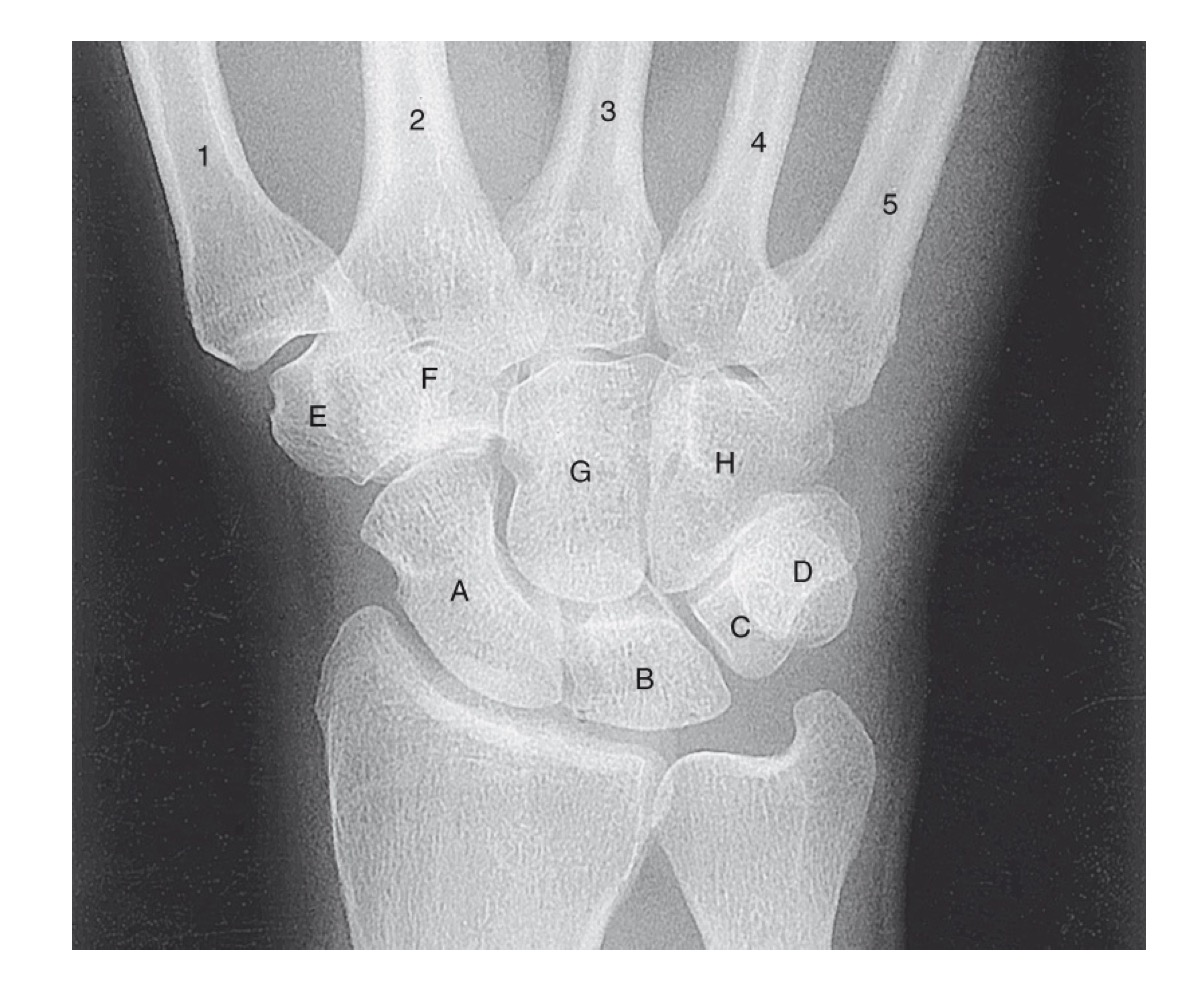

<p>what is A</p>

what is A

scaphoid

49

New cards

<p>what is B</p>

what is B

lunate

50

<p>what is C</p>

what is C

triquetrom

51

<p>what is D</p>

what is D

pisiform

52

<p>what is E</p>

what is E

trapezium

53

<p>what is F</p>

what is F

trapezoid

54

<p>what is G</p>

what is G

capitate

55

<p>what is H</p>

what is H

hamate